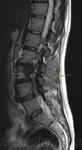

Здравствуйте уважаемы коллеги! Данную патологию вижу в первый раз на Р-грамме позвоночника.

Пациентка, ранее не обследовалась, предыдущих снимков не имеется. Клиника неизвестна. Порылись в книгах, похоже на "Мраморный позвонок". Ваше мнение господа:)

Здравстуйте Валентин Львович, удивляет что высота позвонка не снижена, что он весь такой ровненький и чистенький...только белый среди черных:) С ровными контурами.

Типичный рентгенологический симптом, называемый "позвонок из слоновой кости" (The Ivory Vertebra Sign).

Если бы "это" встретили у ребенка, то на первое место лимфому Ходжкина. Но в данном случае пожилая женщина, на первое место поставил бы метастаз (искать, прежде всего, канцер молоцной железы).

В диффряд предлагается стандартный и известный всем список (Reeder and Felson):

лимфома

миелосклероз

остеобластный метастаз

Пеждет

флюороз

остеопороз